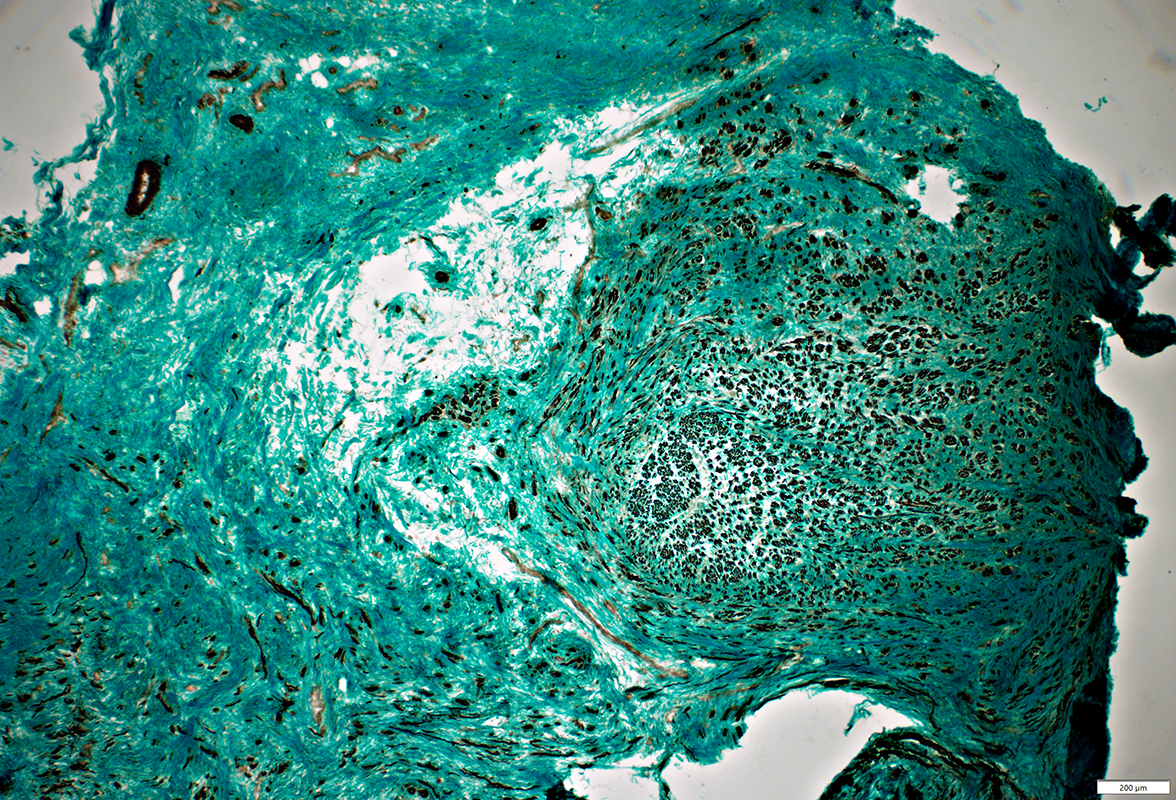

Gomori trichrome stain

Post-regeneration: Small fascicles with varied size and orientations

Neuroma: Multiple small fascicles containing myelinated axons

Neuroma

Varied sizes & orientations of axon clusters (fascicles)

Varied numbers of myelinated & non-myelinated axons in fascicles

Varied numbers of axons in fascicles

Several small fascicles separated by connective tissue

Each fascicle is surrounded by perineurium, 1 or several layers